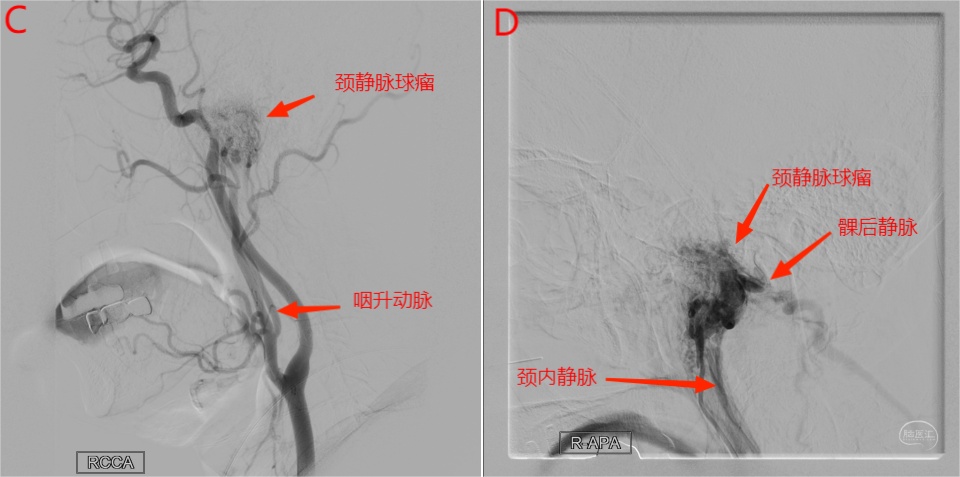

右侧颈静脉球瘤患者进行术前造影及栓塞,咽升动脉神经脑膜支(颈静脉孔支)为主要供血动脉。

图16 A图为轴位增强MRI,显示右侧颈静脉孔内病变强化明显;B图为TOF轴位图像,右侧咽升动脉神经脑膜支位于右侧颈内动脉后内侧,管径明显增粗(左侧显示不清)。

图17 C为右侧颈总动脉侧位造影动脉早期,显示咽升动脉增粗,颈静脉球瘤血供丰富;D图为右侧颈总动脉侧位造影静脉期,颈静脉球瘤血流引流入颈内静脉和经髁后静脉引流入枕下静脉。

图18 E为3D成像,显示咽升动脉及神经脑膜支管径增粗,同时可见咽支及肌脊髓支。F为Xper-CT矢状位重建,显示咽升动脉、咽支、神经脑膜支、颈静脉球瘤和髁后静脉。